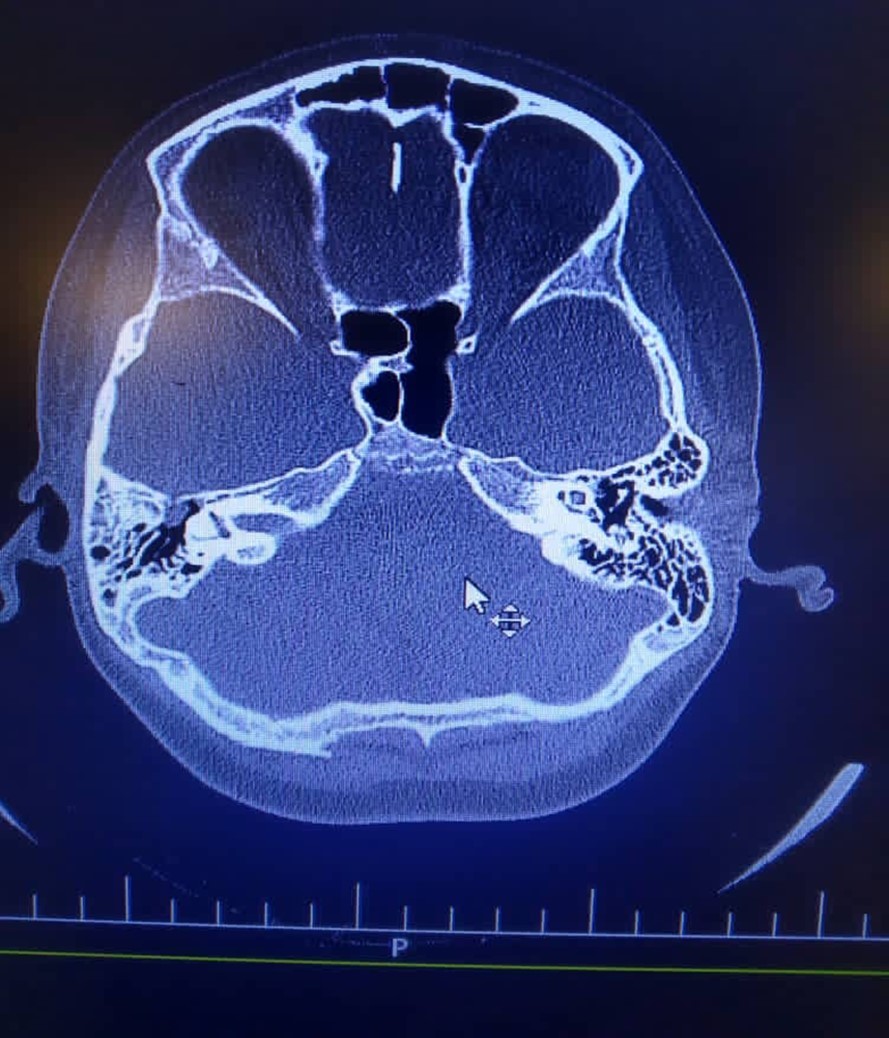

High dose of Cefotriaxone (100 mg/kg/day) and vancomycin (20mg/kg/q6h) were started. Dexamethasone (0.6 mg/kg/day), Phenytoin (5mg/kg/day/BD), Acyclovir (10mg/kg/dose/TDS) and pneumococcal vaccine, were added. He was clearly alert at second day of admission, and he was transferred to the pediatric ward at third day. His abdominal Sonography was normal. A fracture on the right roof of the right tympan and soft tissue density in the middle ear suggestive cholesteatoma reported in Brain Ct scan on day of admission (Figure 1).

Figure 1.There is evidence of fracture on the right roof of the right tympan. Slight opacity of right mastoid air cells is evident. There is soft tissue density in the middle ear and epitympan and preusak cavity suggestive cholesteatoma.